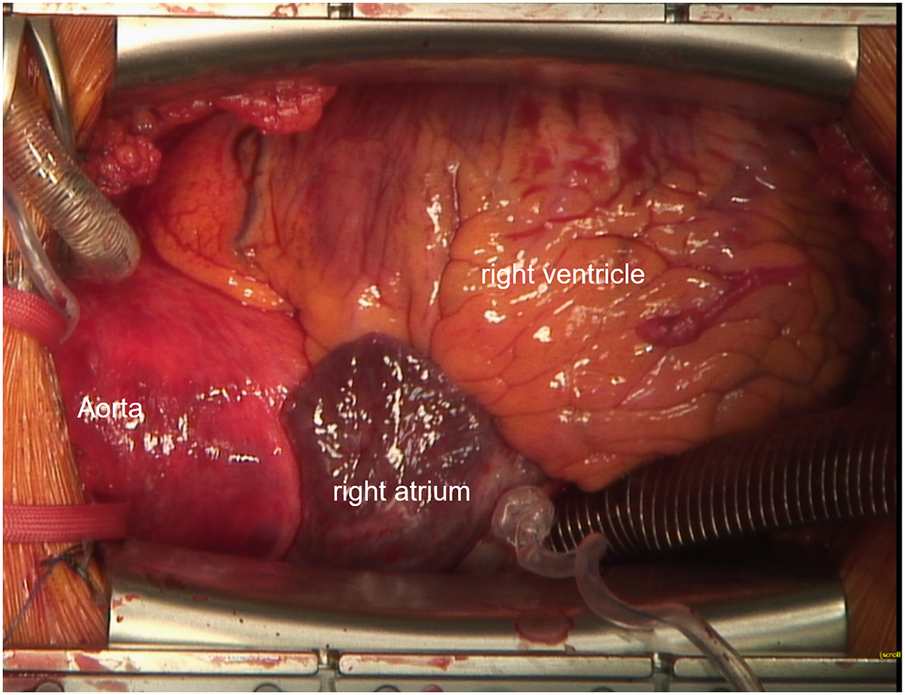

Following median sternotomy and pericardiotomy, cannulation of the ascending aorta as well as the superior vena cava via the right atrium were performed, the latter using a regular two-stage cannula directed cranialwards (Figure 2). CPB was initiated and proved satisfactory considering venous drainage and full relief of the heart. Additional femoral venous cannulation was not required. For cardiac arrest, ice-cold (5–8°C) crystalloid solution was used. Additionally topical cooling with cold water was performed. The aortic valve, aortic root, and ascending aorta were replaced using a mechanical 23 mm conduit. The hemiarch was replaced with a 26 mm tube under hypothermic circulatory arrest (25 min) with selective antegrade cerebral perfusion (SACP). Therefore, after reaching a body temperature of 25°C, SACP was initiated by open direct cannulation of the innominate artery and the left common carotid artery. The left subclavian artery was blocked with a ballon catheter. The total duration of the cardiopulmonary bypass was 4 h and 26 min, and aortic clamp time was 2 h and 46 min.

Figure 2

Intraoperative cannulation. Venous cannulation with a 2-stage cannula into the superior vena cava is shown.